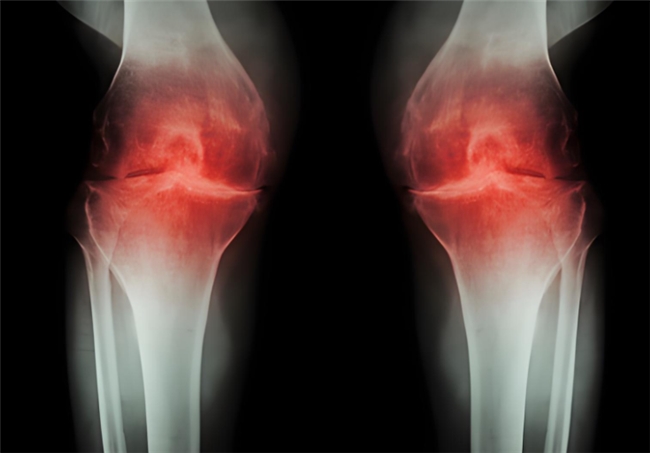

骨關(guān)節(jié)炎作為常見(jiàn)的關(guān)節(jié)退行性疾病,困擾著眾多中老年人乃至長(zhǎng)期勞損的人群。患者不僅會(huì)頻繁遭遇關(guān)節(jié)疼痛、腫脹、僵硬等不適,隨著病情發(fā)展,還可能出現(xiàn)活動(dòng)受限、關(guān)節(jié)變形,進(jìn)而影響走路、上下樓等日常行為,讓生活質(zhì)量大打折扣。更令人擔(dān)憂的是,骨關(guān)節(jié)炎的病程一旦進(jìn)入中晚期,治療難度和痛苦都會(huì)明顯增加。因此,及早干預(yù)至關(guān)重要。而氨基葡萄糖就是臨床常用的治療藥物之一,但它還有鹽酸和硫酸氨基葡萄糖之分,到底鹽酸和硫酸氨基葡萄糖的作用與功效有什么不同?骨關(guān)節(jié)炎患者如何選擇呢?

鹽酸和硫酸氨基葡萄糖膠囊都是氨基葡萄糖類藥物,能為關(guān)節(jié)軟骨提供合成原料,在促進(jìn)軟骨基質(zhì)的修復(fù)與再生的基礎(chǔ)上,補(bǔ)充關(guān)節(jié)滑液以減少摩擦,同時(shí)通過(guò)抑制關(guān)節(jié)腔內(nèi)的炎癥因子,從多個(gè)方面幫助延緩骨關(guān)節(jié)炎的進(jìn)展[1],但它們?cè)谂R床療效上卻存在一定差異。

根據(jù)國(guó)際醫(yī)學(xué)四大期刊之一《美國(guó)醫(yī)學(xué)會(huì)雜志》上發(fā)布的一項(xiàng)研究表明,硫酸氨基葡萄糖在緩解膝骨關(guān)節(jié)炎疼痛、改善關(guān)節(jié)活動(dòng)功能方面,效果優(yōu)于鹽酸氨糖等33種骨關(guān)節(jié)炎常用藥[2]。還有相關(guān)研究顯示,硫酸氨基葡萄糖不僅能延緩關(guān)節(jié)間隙變窄,還能從根源改善關(guān)節(jié)結(jié)構(gòu)、減緩磨損。而鹽酸氨基葡萄糖在這一關(guān)鍵指標(biāo)上的效果尚未明確。因此,在關(guān)節(jié)保護(hù)的“確切性”上,硫酸氨基葡萄糖顯然更具優(yōu)勢(shì)。